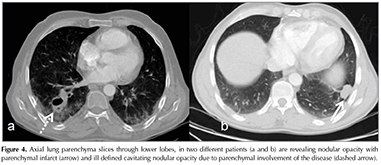

Parenchyma signs on CT were sub-pleural alveolar infiltrates, consolidation, ill-defined round opacity, focal atelectasis, and cavitation. At least one of the following lung parenchymal findings, including ill-defined nodular infiltration, sub-pleural alveolar infiltrates, ground glass attenuation, mosaic attenuation, focal atelectasis, and consolidation and cavitation, detected on CT in 14 of patients (14/16). Sub-pleural alveolar infiltrates (9/16), and focal atelectasis (8/65) and ill-defined nodular opacity (5/16) were more common lesions in all patients, mostly seen in the lower lobes. The other lung lesions were consolidations (in 3 patients related with pulmonary infarct), cavitation (in 3), and mosaic attenuation (in 1 patient). One of patients with isolated parenchyma involvement had right upper lobe ill-defined nodular opacity with surrounding ground glass attenuation.

The spectrum of lung parenchyma CT findings is diverse and these may be confused with other common entities, such as infection, particularly in patients under immunosuppressive treatment. They are seen frequently in cases of PAI, but isolated lesions reported are attributed to microscopic pulmonary vascular disease (3,13.) In their study, Zhang et al. discussed that isolated lung lesions related to BD should be suspected in patients with a poor response to antibiotherapy (13). In our study, 9 of 12 patients with PAI revealed parenchymal changes in CT and plain X-Ray. The most common CT findings were ill-defined nodular opacities, sub pleural alveolar infiltrates/consolidations and focal atelectasis, cavitation (Figure 4). Isolated parenchyma involvement of BD is also another finding which has scarce known properties. Zang et al. reported isolated parenchymal involvement in 6 of 15 patients (13). They also claimed that the clinical outcome of this group is better than those with PAI radiologic ally. In this entity the findings are related to micro vascular involvement. Although not histopathologically confirmed, 1 of our patients had parenchyma lesions without evidence of lobar, or segmental PA involvement. These lesions appeared under antibiotics treatment and regressed after the administration of immunosuppressive agents.